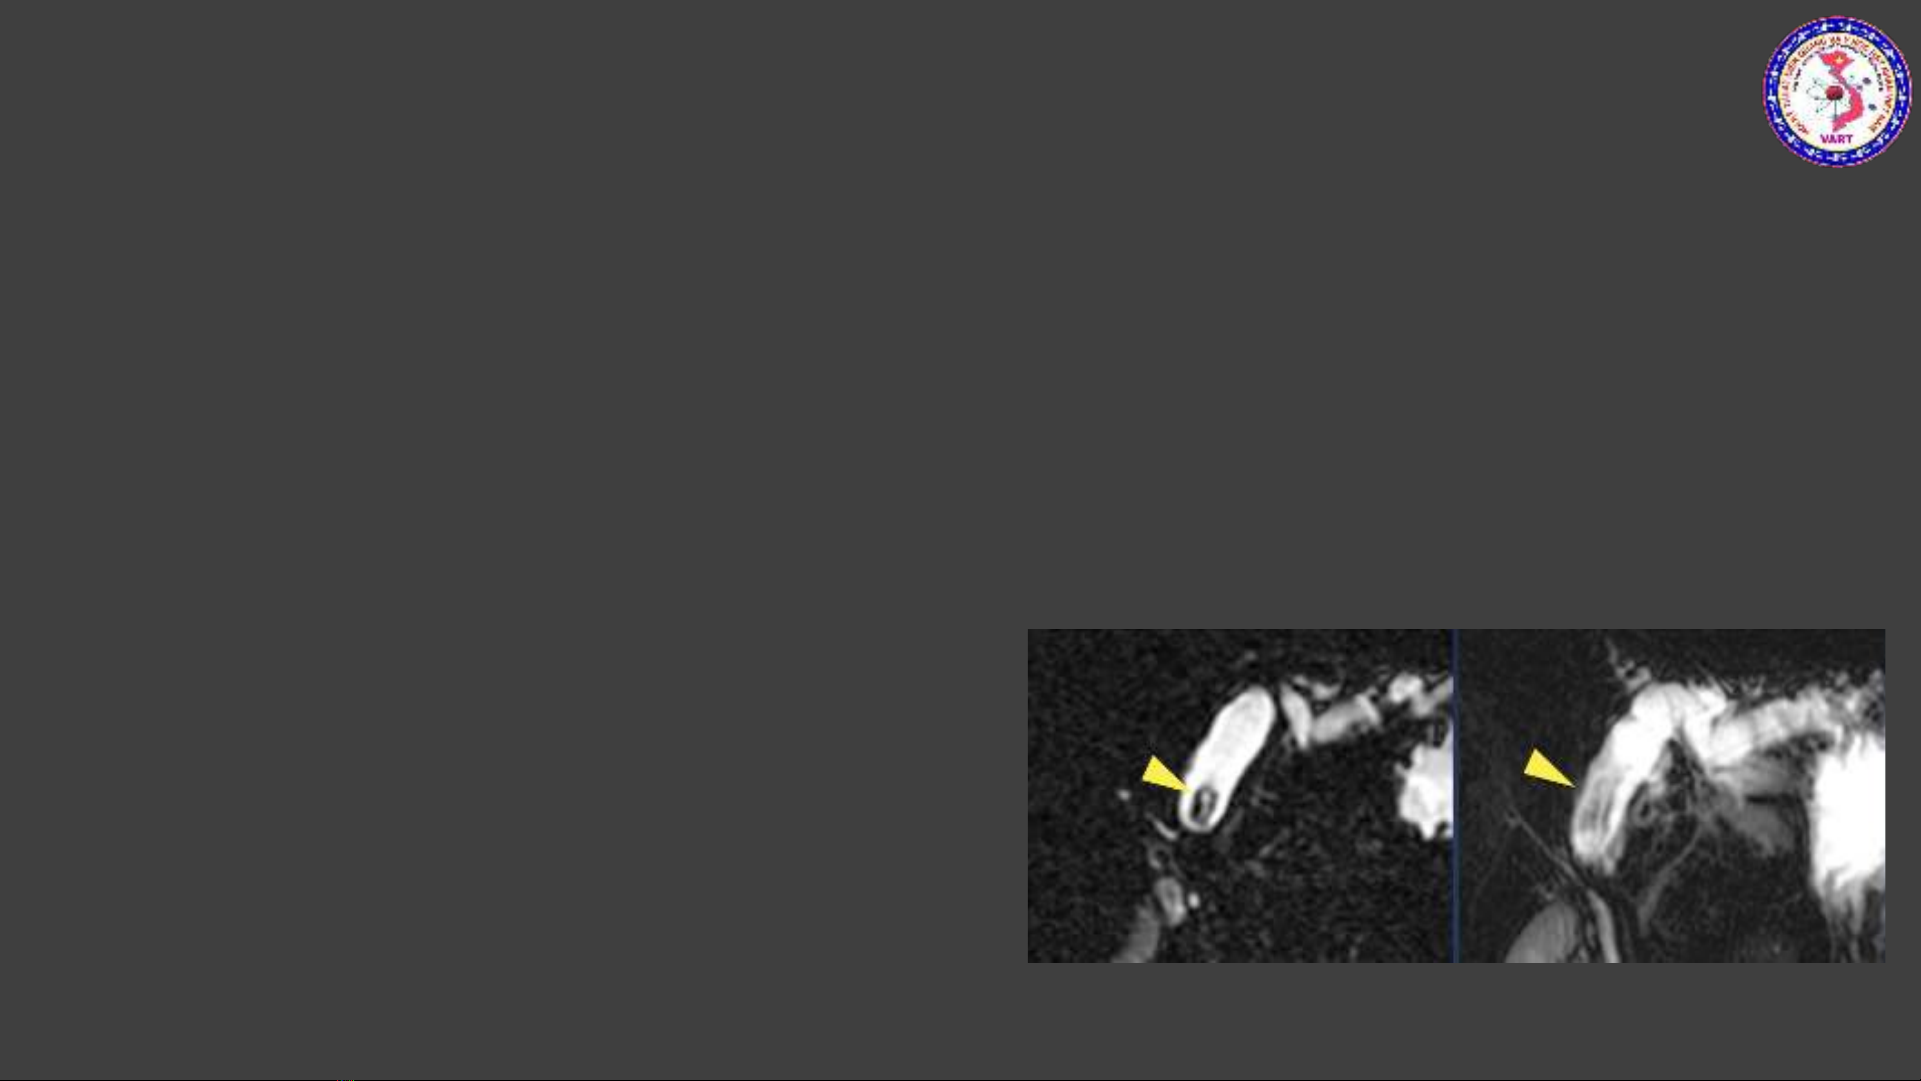

•Dựa trên nền tảng FSE 3D

•Sử dụng TE rất dài, từ 600-1200ms. Mục đích để các mô xung quanh bị bão hòa hoàn toàn, chỉ

còn lại những thành phần dịch tự do, dịch di chuyển chậm có thời gian T2 dài -> tăng tín hiệu